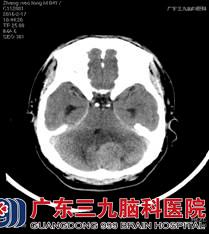

张先生发病以来神志清楚,查体结果显示:神经系统查体未见明显异常,头颅磁共振提示“左侧小脑占位性病变”。完善了所有术前检查及准备,神经外六科的金鑫医生为其实施了左侧小脑半球肿瘤切除术,手术过程顺利,病理结果回报:血管周细胞瘤。

术前CT及核磁共振